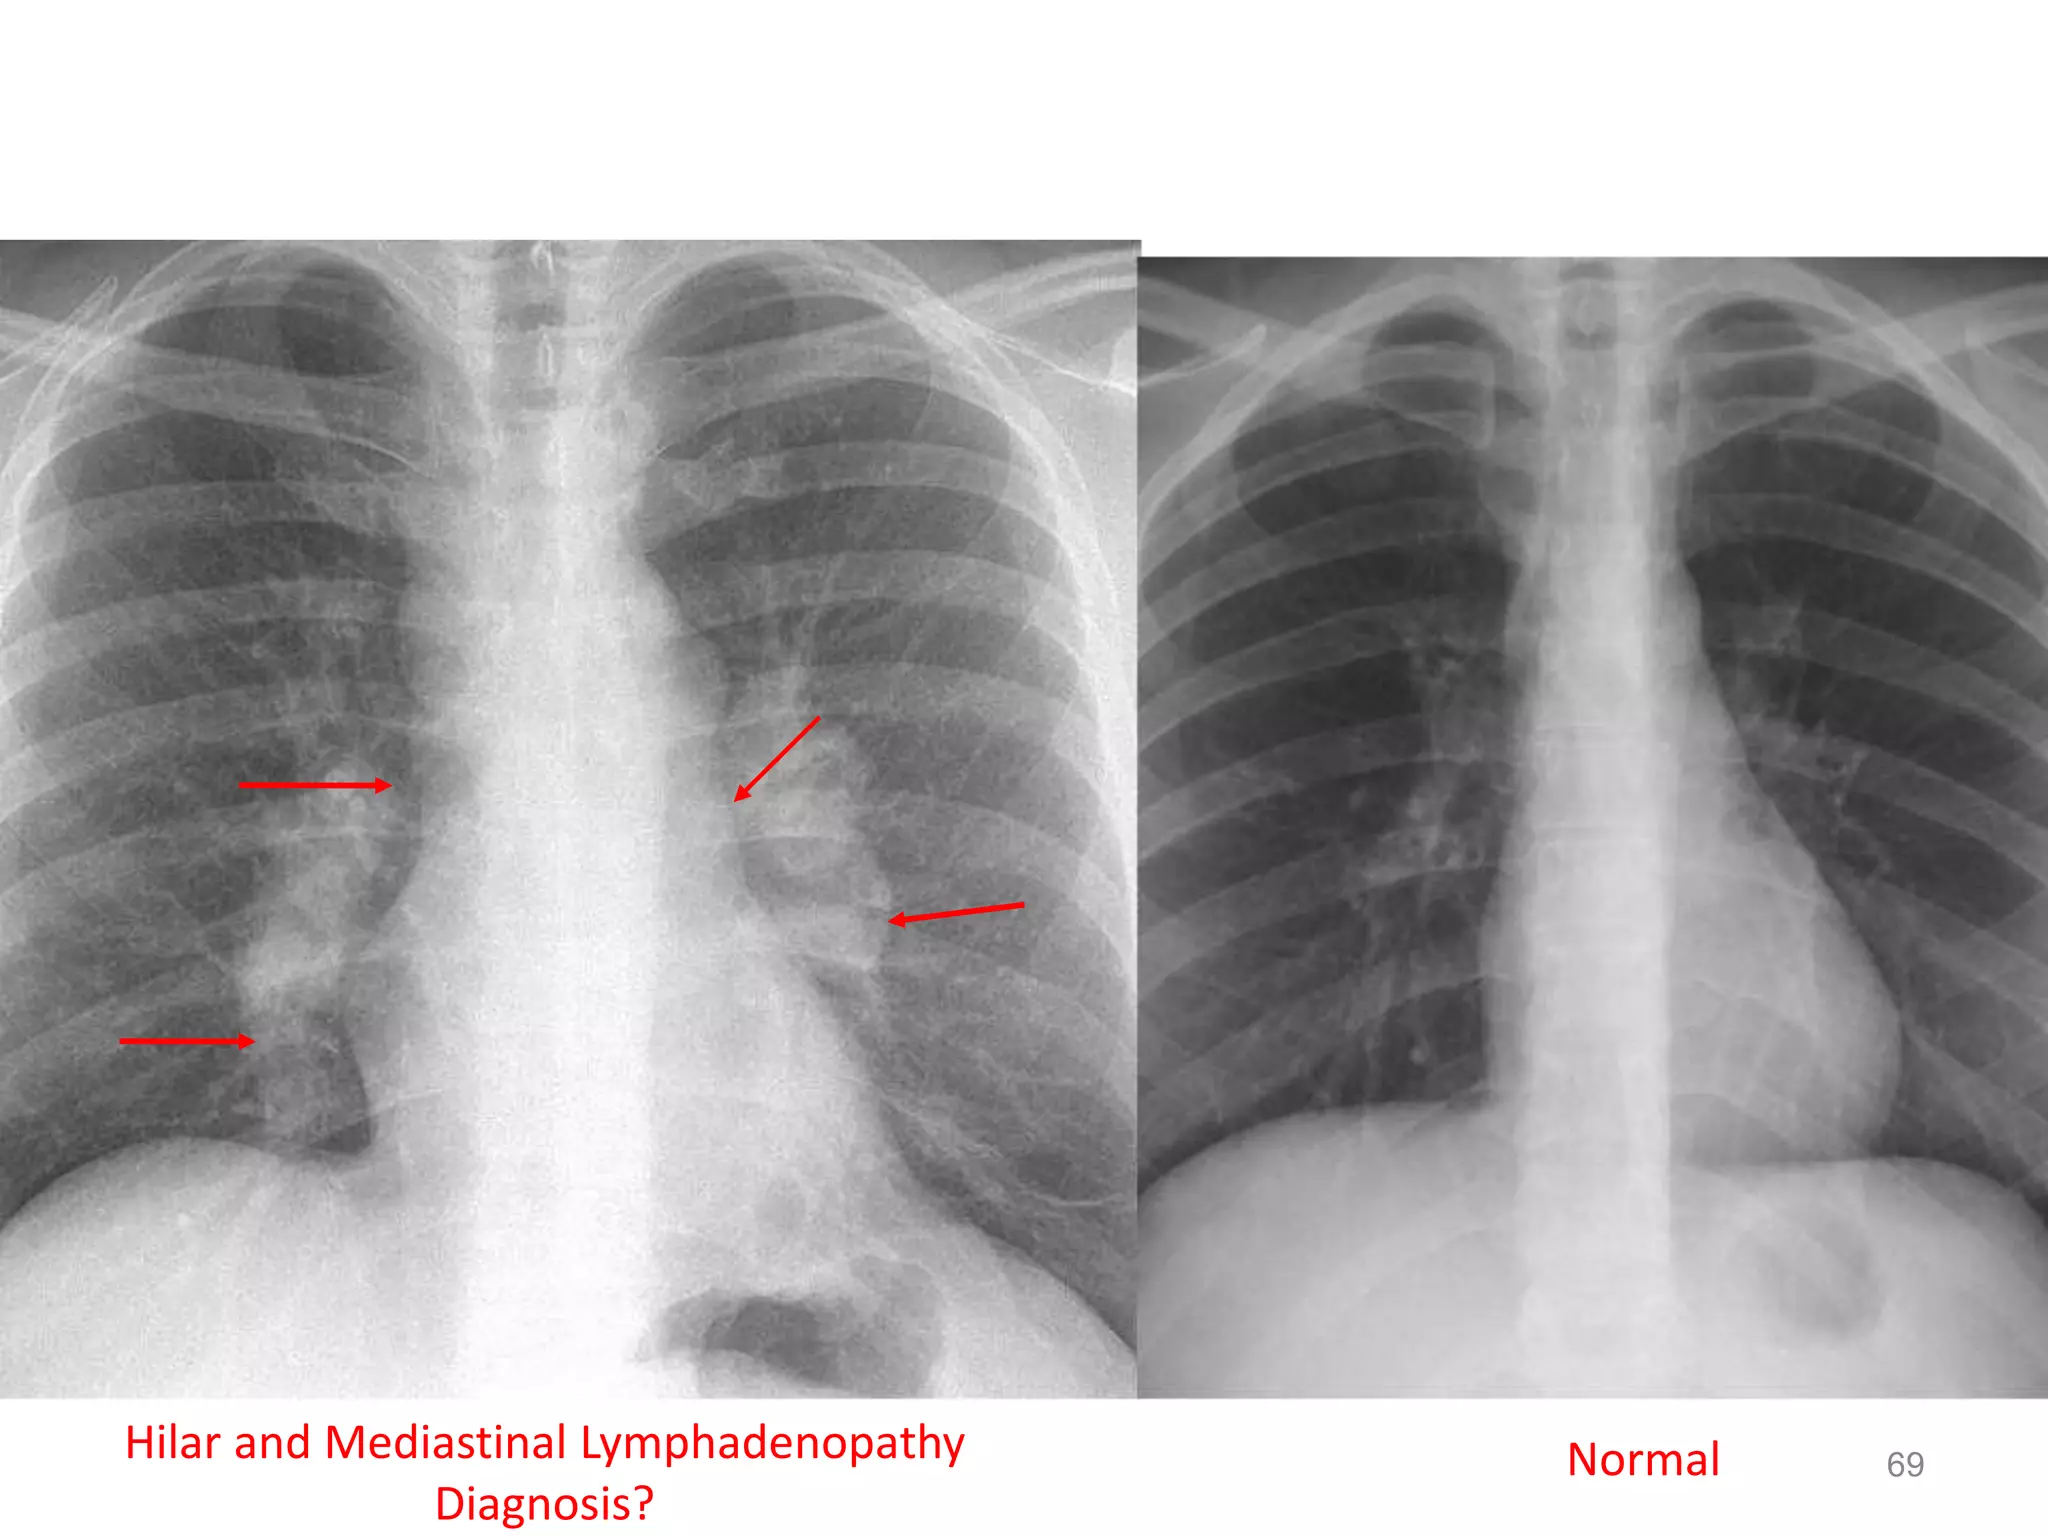

69154 slides NormalHilar and Mediastinal Lymphadenopathy

Diagnosis?

69154 slides NormalHilarand Mediastinal Lymphadenopathy Diagnosis? 69